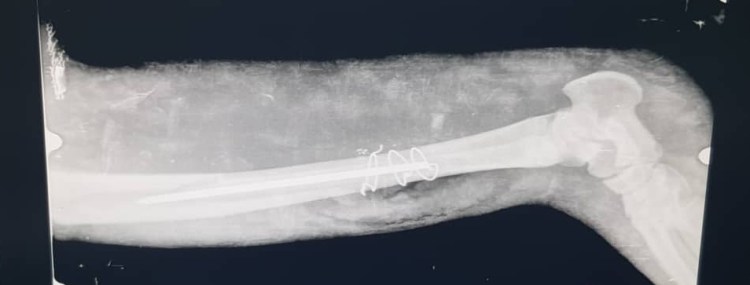

Le fait est qu’hier notre jeune amie a subi une longue intervention chirurgicale : 3 vétérinaires chirurgiens se sont penchés sur son cas pour lui placer une broche et des fils de cerclage.

L’opération a duré 2h et demi et nous sommes très reconnaissants de l’intervention des chirurgiens PO Dr Binémo Clément, Pr Dr Lenge Moïse et le Dr Binemo Jean Claude.

Grâce à leurs expériences et leurs connaissances, la fracture a pu être opérée avec les moyens du bord car, je le rappelle, ici, beaucoup de choses font défaut et nous devons à chaque fois composer avec ce que l’on a, avec ce que l’on trouve! Pour Bapu, nous avons fait du mieux que l’on a pu!